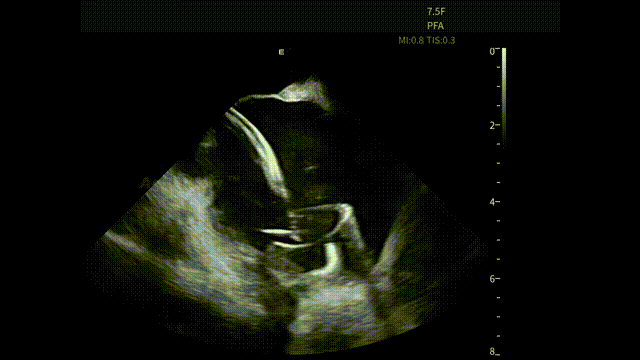

术中,基于AgileView™ ICE 7.5F的产品优势,蒋晨阳主任团队将ICE导管打A弯跨三尖瓣进右室,松弯卡室上嵴,顺转后打到左房长轴切面,以便更好地进行导管封堵/贴靠与位置的判断,在AgileView™ ICE实时影像的指导下,PulseSelect™ 脉冲消融导管安全进入左心房,先后完成双侧肺静脉隔离及MTI、roofline、后壁BOX、SVC隔离, ICE下可见导管贴靠良好,整个消融过程顺利,消融时间约50分钟。术后患者恢复良好。

左房长轴一嵴部贴靠

RSPV

SVC